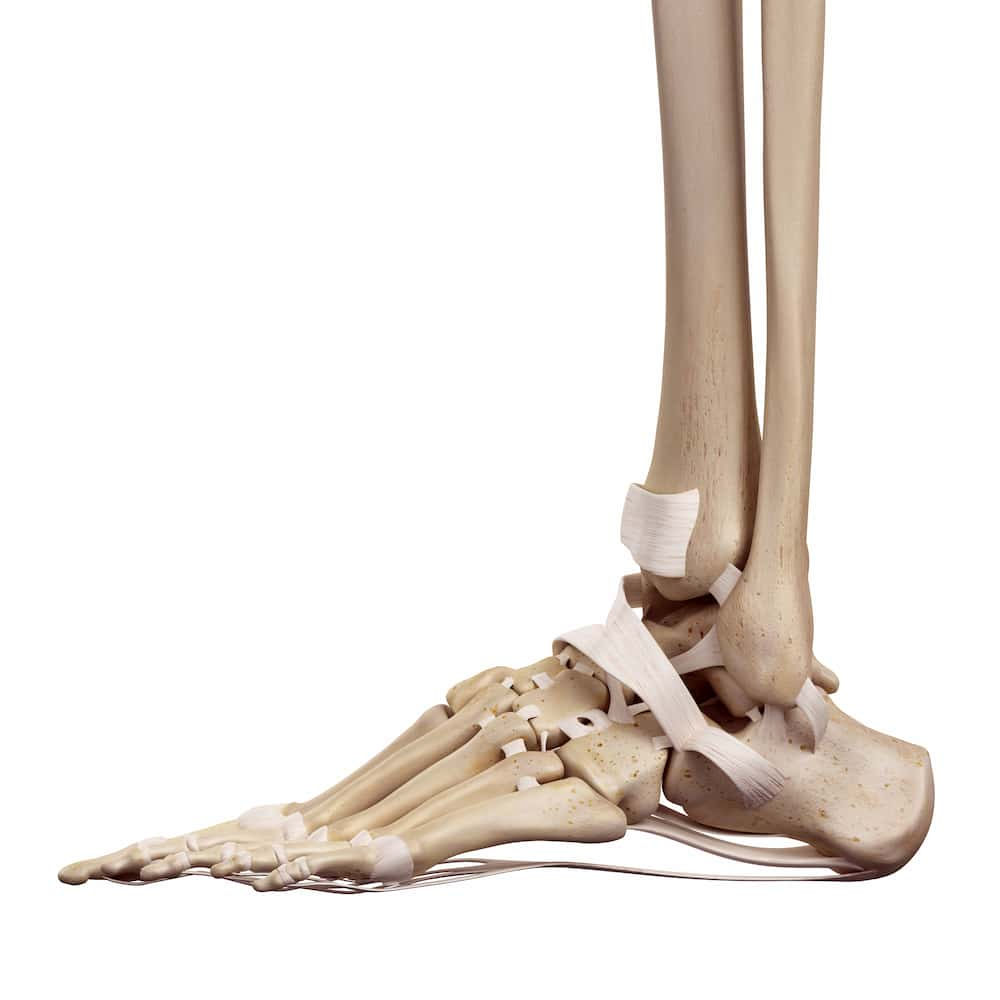

There are many different types of fractures; they all essentially mean the same thing i.e. that one or more of the bones around your ankle joint have been broken.

It really isn’t easy to break a bone in your body. Your bones are incredibly strong and can take an awful lot of knocks, bumps and injuries and will generally not complain. You are more likely to find that you may upset the soft tissues (ligaments, muscles and tendons) following an injury than your bones.

The most common way to fracture an ankle is by ‘turning or rolling’ your ankle. This normally happens whilst walking or running, as your foot goes underneath yourself and your body weight pushes down on the ankle/foot, causing the injury.